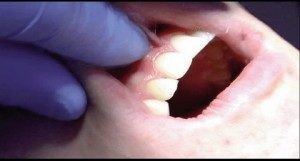

So what can soft-tissue lasers do? Probably a lot more than you think. First, diode lasers can cut and shape soft tissue, which gives us the opportunity to remove lesions, (fibromas), release frenoms, recontour gingiva, and trough around crown preps. Usually this can be accomplished with little bleeding, minimal collateral tissue damage, and better healing. Unlike an electro- surge unit, diode lasers can be used around crowns, ortho brackets, and implants. Diode lasers can also be utilized to whiten teeth. Diode lasers seek pigment so it makes sense that they would be effective at removing pigment and stain in the whitening procedure. I feel the results are similar or better than any in-office whitening system available, with less sensitivity and a shorter appointment time. (I have seen great results in as little as ten minutes utilizing a laser to whiten teeth.)